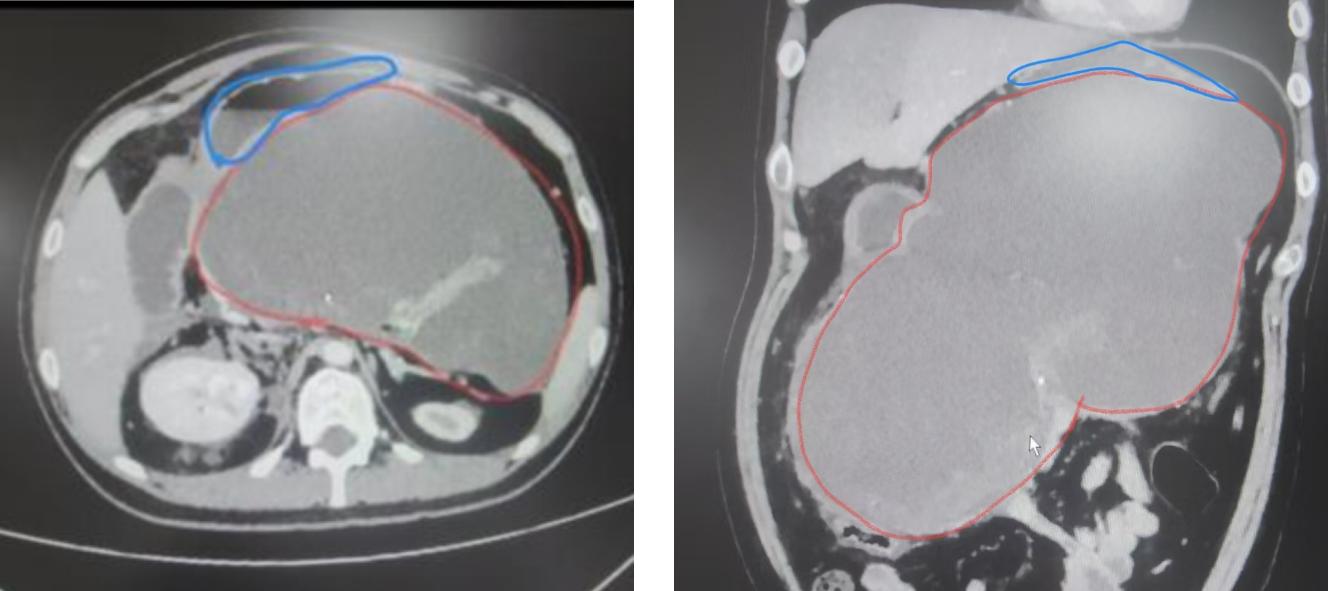

这位患者为20岁男性,因“反复腹痛1月余,再发伴腹胀1天”入院。1月前确诊急性胰腺炎,随后出现腹围增大、呕吐、腹胀等压迫症状。增强CT提示胰周巨大假性囊肿形成,最大截面约13.1×21.0cm,胃及及十二指肠严重受压,无法正常进食。

术前CT(胰腺巨大假性囊肿,胃腔明显受压)